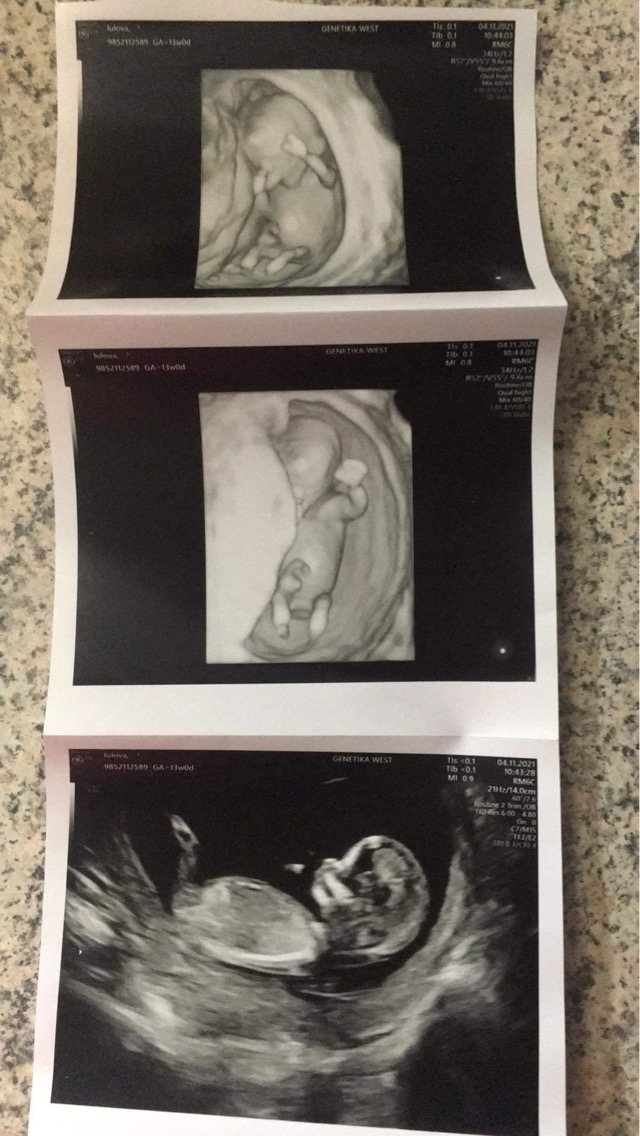

Takže prosím, jsem 12+1 - vše je v pořádku jen nám nechce říct pohlaví - dostali jsme fotky a jedna z nich - viz příloha, mi přijde že je to kluk . Holky,odbornice - měly jste něco podobného a co se z toho vyklubalo?